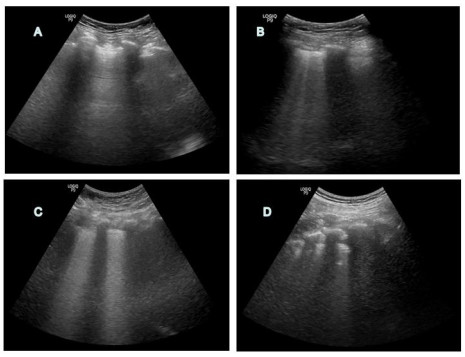

所有患者均按照腹腔感染常规治疗方案进行治疗,符合拔管的按拔管流程有序进行,行2 h SBT,通过SBT后给予拔除气管导管。是否需要再插管由临床医师根据患者病情决定。拔管前LUS评估方案:由受过训练的2名ICU医师完成肺部超声检查,使用2~4 MHz凸型探头对患者左右前胸壁、侧胸壁、后胸壁共12个区域进行检查并记录,超声通气模式定义:(1)正常通气(N):A线或1条或2条孤立、垂直B线;(2)中度肺通气丧失:多发融合B线;(3)重度肺通气丧失:多重聚结、垂直的B2线;(4)肺实变(C):肺组织影伴支气管充气征。N=0,B1线=1,B2线=2,C=3。每个检查区域评分之和为LUS总分。分值0-36分[12]。见图 1。

| A:正常通气;B:中度肺通气丧失;C:重度肺通气丧失;D:肺实变 图 1 肺部超声通气模式影像图 Fig 1 Images of lung ultrasound ventilation mode |